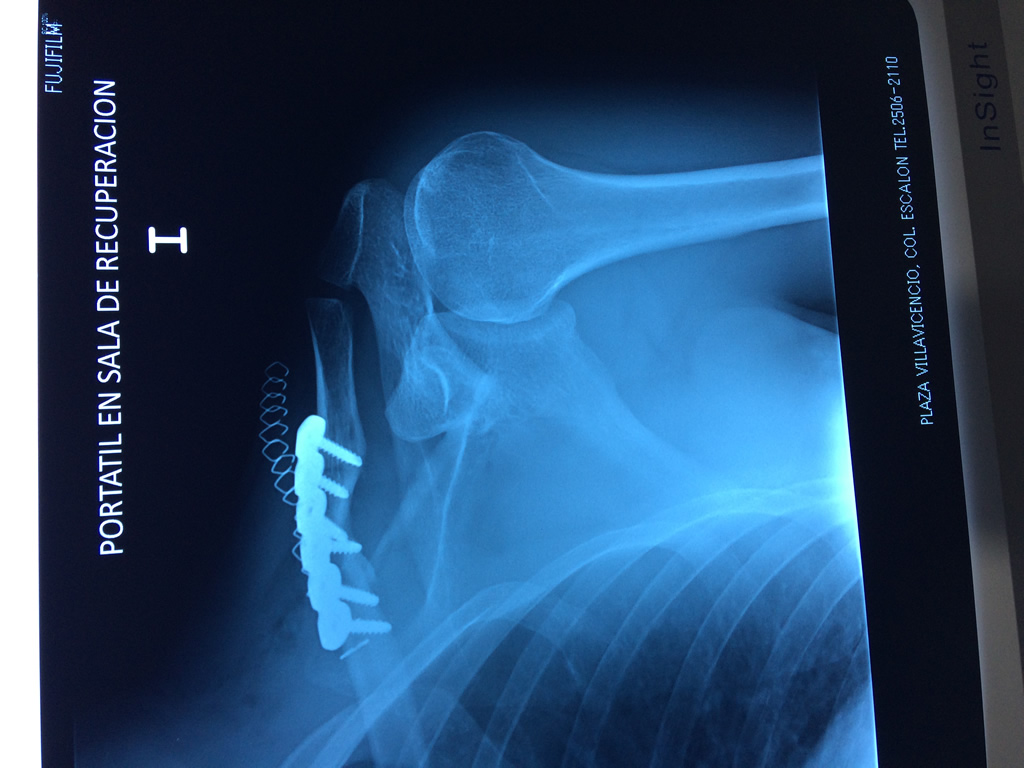

Cirugias en El Salvador - Clavícula

La clavícula es un hueso largo, con forma de "S" itálica, situado en la parte anterosuperior del tórax. Junto con la escápula forman la cintura escapular. Se puede palpar por toda su longitud y se extiende del esternón al acromion de la escápula, siguiendo una dirección oblicua lateral y posterior.